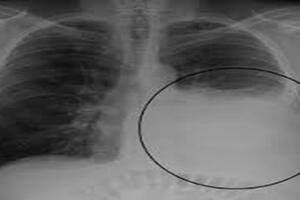

Cần hỏi bệnh và thăm khám kỹ các triệu chứng bệnh lao trước khi sàng lọc lao tiềm ẩn. Chụp X quang ngực nếu nghi ngờ lao tiến triển. Bệnh nhân có triệu chứng lâm sàng và bất thường trên Xquang ngực cần được làm xét nghiệm thăm dò kỹ hơn để chẩn đoán lao tiến triển.

Đờm và phim X quang ngực bình thường

Có thể gặp hình ảnh bất thường trên phim X quang ngực hoặc vi khuẩn lao có trong đờm